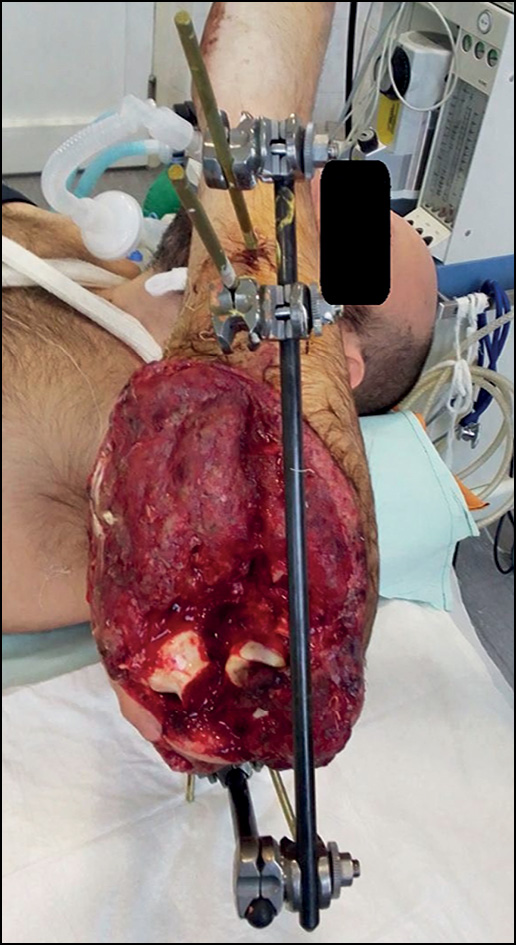

При ограниченных дефектах использовали первично-отсроченные или вторичные швы, пластику местными тканями. При обширных комбинированных дефектах у 5 (20%) пациентов применяли несвободный кожно-мышечный (торакодорзальный) лоскут с установкой цементного антибактериального спейсера (рис. 5).

Рис. 5. Рентгенограмма правого локтевого сустава пациента А. с установленным антибактериальным цементным спейсером.

Fig. 5. X-ray of patient A. right elbow joint with an antibacterial cement spacer installed.

Военнослужащий Д., 25 лет. Из анамнеза и представленной медицинской документации известно, что во время выполнения боевой задачи пациент получил осколочное ранение области правого локтевого сустава. Первая помощь оказана на месте. В первые сутки после ранения выполнена первичная хирургическая обработка, наложен стержневой аппарат внешней фиксации КСТ, проведена медикаментозная терапия. На 10-е сутки после ранения пациент доставлен авиатранспортом в ФГБУ «Главный военный клинический госпиталь им. Н.Н. Бурденко» Минобороны России. По результатам осмотра и обследования установлен диагноз: осколочное сквозное проникающее ранение правого локтевого сустава с внутрисуставным оскольчатым переломом проксимальных метаэпифизов обеих костей предплечья с дефектом костной ткани. Посттравматическая невропатия локтевого и лучевого нервов (рис. 11).

Рис. 11. Пациент Д.: а — внешний вид раны при поступлении, b — рентгенограммы при поступлении.

Fig. 11. Patient D.: a — appearance of the wound upon admission, b — radiographs upon admission.